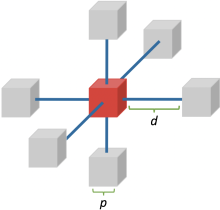

2.4 MIND

另外的一个loss function就是模态独立邻域描述子(Modality Independent Neighbourhood Descriptor,MIND),MIND是一个描述每个voxel周围局部模式的特征。这是通过观察中心patch和固定距离外的patch之间的相似性来计算的。基于MIND的相似函数背后的假设是,即使在不同的图像模态下,voxel周围的local patterns也应该是相似的,因此我们希望最小化我们所配准的两幅图像之间的MIND特征差异。

MIND由一个距离向量 和path size

和path size 来参数化,为了计算基于MIND的损失函数,我们希望看到6邻域patch与中心patch的相似性.

来参数化,为了计算基于MIND的损失函数,我们希望看到6邻域patch与中心patch的相似性.

图2.3 用于计算 的6邻域patch视图,由参数 path size

的6邻域patch视图,由参数 path size 和distance

和distance  来参数化。

来参数化。